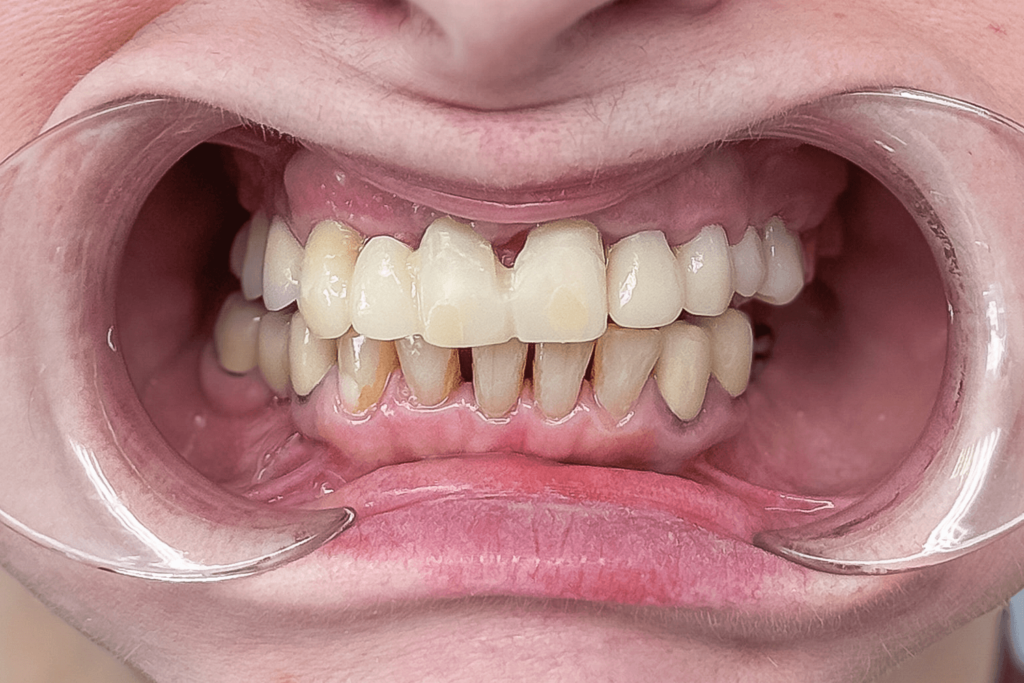

Повторное сканирование и временное протезирование

Подготовленные к протезированию зубы врач отсканировал интраоральным сканером для последующего изготовления постоянных ортопедических конструкций. Сразу после сканирования врач зафиксировал временные зубные протезы, в том числе, для окончательного согласования формы и размера зубов.

8 ЭТАП

Постоянное протезирование конструкциями из диоксида циркония

Несколько дней спустя пациентке сняли временные конструкции и зафиксировали постоянные из диоксида циркония (цвет Bleach 2). Мостовидные протезы в области зубов 14-16, 11-13, 23-27, 35-37, 44-46 и одиночные коронки на зубах 2.1, 2.2, 4.3, 4.2, 4.1, 3.1, 3.2, 3.3, 3.4. Где были старые импланты, зубы 1.4 и 1.6 на них зубной мост закреплен винтовой фиксацией, все остальные конструкции — цементной.